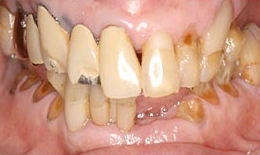

インプラント症例(8)72歳 男性

治療後

治療方法

上顎

保存困難な歯を抜歯後、インプラントを1本埋め込んで、セラミックスクラウンを被せた

下顎

保存困難な歯を抜歯後、インプラントを2本埋め込んで、セラミックスクラウンを被せた